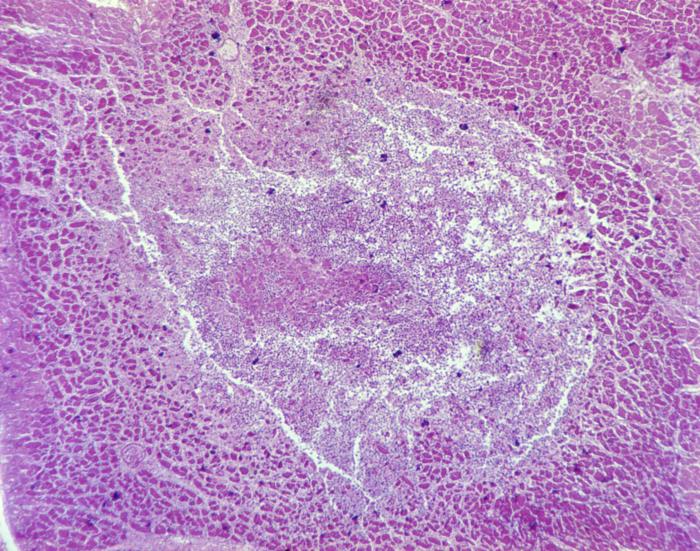

Under 52X magnification, this photomicrograph shows a cardiac muscle tissue specimen obtained from a patient with bacterial endocarditis. Visible is a lightly stained intramyocardial abscess containing necrotic cellular debris and numerous white blood cells, reflecting the acute infectious process affecting the heart muscle.